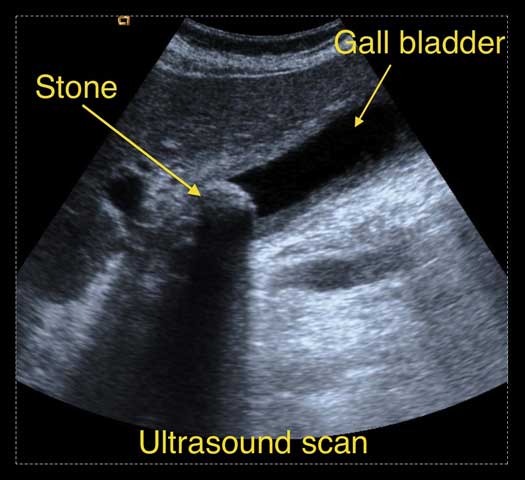

How are gallstones diagnosed?When gallstones are suspected, the first test to be done is an abdominal ultrasound. This is a simple, fairly painless and straightforward test, and does not involve the use of x-rays. Ultrasound waves are used to create images of organs and if stones are present, the sound waves will bounce off them and show them up (see illustration).

Occasionally, other tests may be required, such as an MRI scan (referred to as MR cholangio-pancreatography or MRCP), CT scan, or radio-isotope tests such as HIDA scans. An MRCP will show the anatomy of the liver and the gall bladder, the bile duct, as well the surrounding organs such as the pancreas (see illustration).